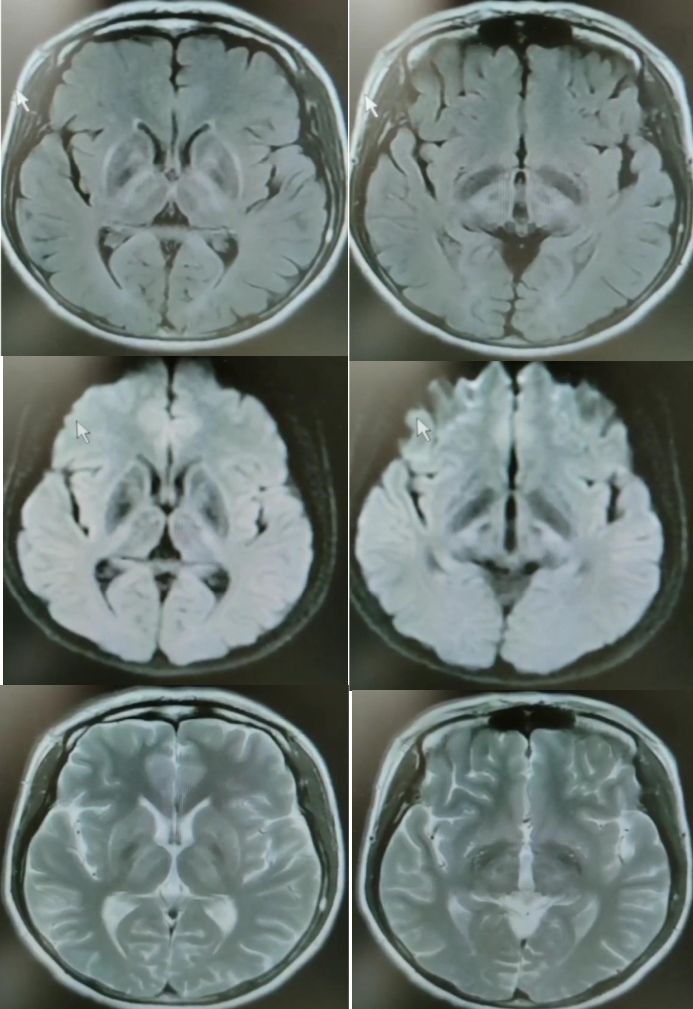

发病24小时磁共振:

答案:脑型脂肪栓塞综合征。患者做了自体脂肪填充术。脂肪栓塞综合征(fat embolism syndrom,FES)是指直径为10~40μm的血管内脂肪颗粒阻塞血管腔而引起的一系列病理生理改变的临床综合征。FES常发生于骨创伤及骨手术病人。FES潜伏期为6~24h,FES 的典型三联征为低氧血症、意识障碍和瘀斑。

答案:*洛因海**海绵状白质脑病。*洛因海**海绵状白质脑病(heroin spongiform leukoencephalopathy,HSLE)是因烫吸或静脉注射*洛因海**而引起的中枢神经系统器质性疾病。临床和影像特点如下:

4. CT和MRI影像显示病灶位于脑白质区,呈广泛、对侧性损害(小脑半球、脑干、内囊后肢、胼胝体压部及大脑半球后2/3),其中小脑受累严重,小脑中线两旁、边界清楚的对侧性类圆形或蝴蝶样病灶最具特点(蝶翼征);在脑干部位,若同时有红核及网状结构受累,则可见“蟹钳征”;在内囊后肢则呈“八字征”。病变在T1W为低信号,T2WI为高信号,FLAIR为高信号,且增强扫描一般无强化.5.病理显示脑白质空泡样变。